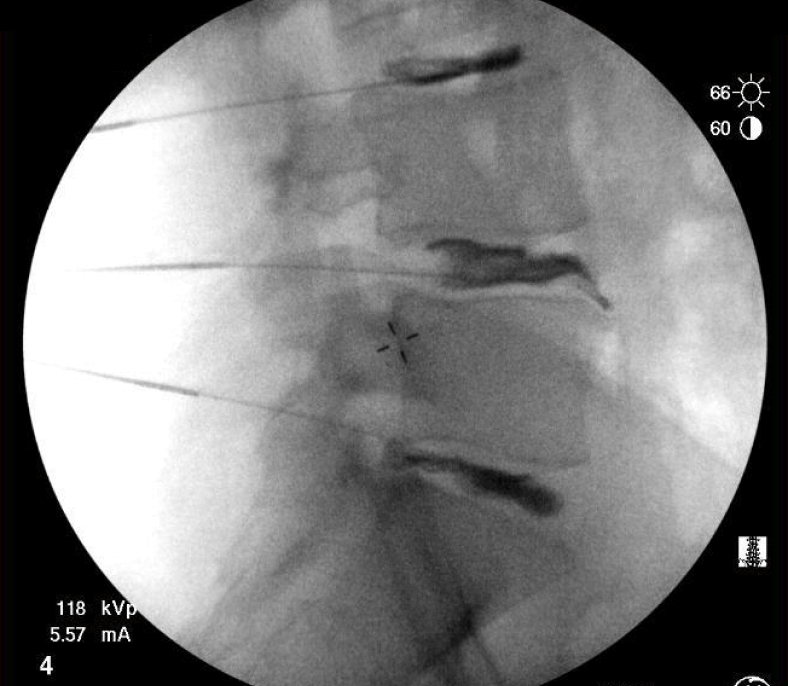

Bone Marrow Aspirate Extraction. Your procedure is done in 2 steps, extraction and injection. First a small amount of your bone marrow is extracted under X-Ray guidance. The bone marrow is centrifuged to concentrate the cells.

Intradiscal Injection. The concentrated bone marrow extract is then injected into your intravertebral disc. The entire procedure is done live under x-ray guidance.